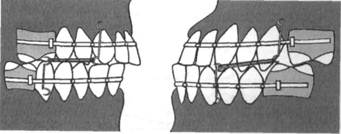

Для лечения зубочелюстных аномалий тяжелой степени обычно используют головную шапочку или шейную опору с лицевой дугой, которая имеет внутри- и внеротовую части.

В зависимости от направления действующей силы возможно различное перемещение зубов. Действующая сила, направленная по са-гиттали, позволяет перемещать зубной ряд в дистальном направлении. Такая необходимость возникает при лечении сагиттальных аномалий окклюзии. Сила, направленная вертикально, способствует задержке вертикального роста верхней челюсти, зубоальвеолярному внедрению.

Сила, являющаяся равнодействующей двух сил (сагиттальной и вертикальной), направленная к козелку уха, создает вращательный мо-

мент для верхней челюсти и позволяет производить зубоальвеолярное внедрение боковых зубов.